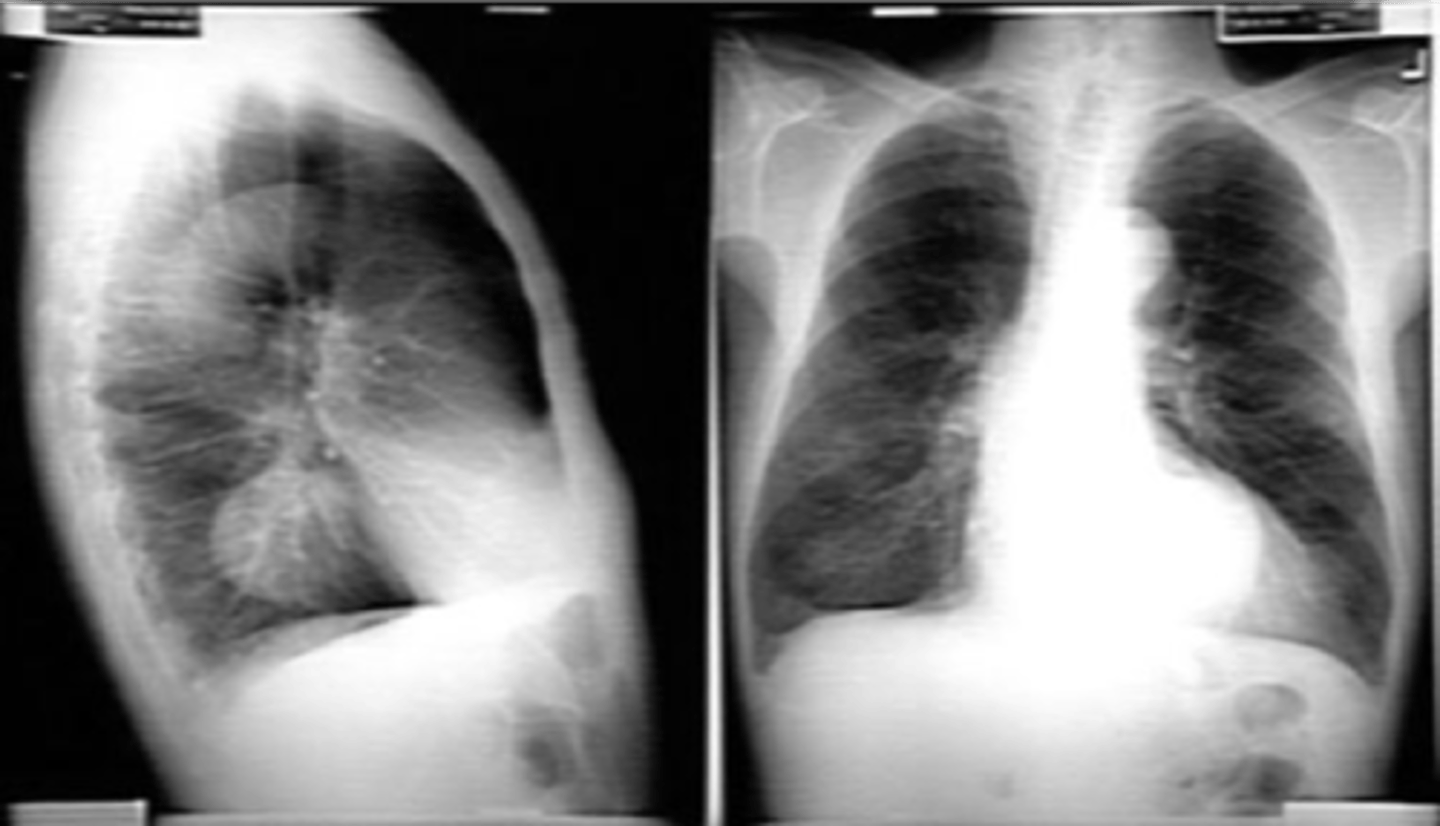

COPD/Emphysema

knowt flashcard image